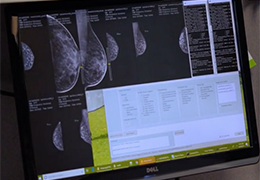

人工智能不再是一项抽象的承诺。Eclipse 引擎为 ImageView 软件提供支持,将 AI 付诸于无可争议的行动,即通过成像智能、工作流智能和分析智能推动产生具体、可衡量的结果。

Eclipse 成像智能功能提供强大的处理能力和最佳质量的影像,同时减少质量错误并提高剂量效率。

凭借 AI、专有算法和先进的影像处理能力,提供出色的影像质量和无与伦比的诊断信心。

这些功能利用数字控制面板分析运营、业务和临床绩效。

使管理员能够跟踪关键参数,包括平均曝光率、拒绝的影像和探测器统计信息。

帮助确定需要改进的方面,支持为员工和部门制定适当的改进计划。